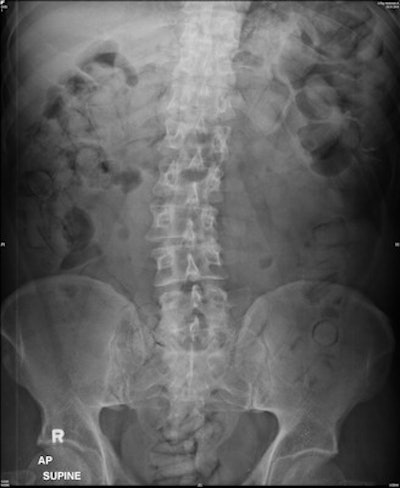

This patient swallowed 64 packs and displays the double condom sign (packs imaged longitudinally) and halo sign (packs imaged transverse). The forensic imaging inexperienced group counted 31 to 50 packs, whereas the forensic imaging experienced group both counted 60 packs -- again under-reporting the entire internal payload. All images courtesy of Dr. Patricia Flach.There is little research on the accuracy of plain abdominal radiography in methamphetamine drug carriers, although there has been a significant increase of meth in Asia. Dr. Saiful Nizam and Abdul Rashid, from the department of radiology at University Putra Malaysia in Selangor, and colleagues retrospectively evaluated the sensitivity, specificity, and accuracy of abdominal DR for identifying the internal payloads of methamphetamine in drug mules.